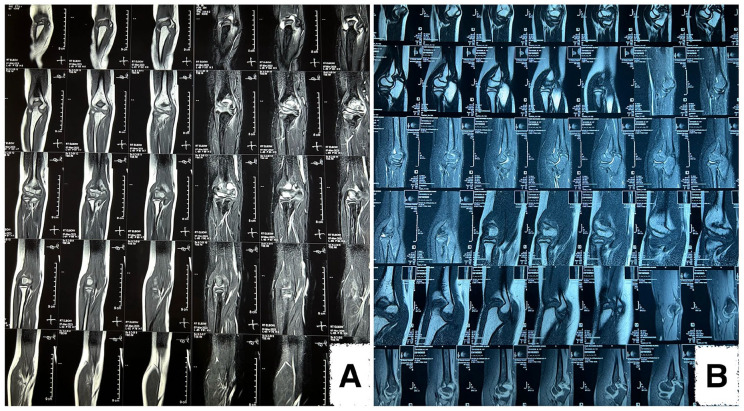

慢性复发性多灶性骨髓炎(CRMO)是一种罕见的非感染性炎症性疾病,发病率为 1 至 2/106,可引起多发性溶解性骨病变。目前还没有治疗 CRMO 的成熟方案,因此,目前的做法主要是经验性的。唑来膦酸(ZA)用于治疗青少年CRMO的数据很少。一名 12 岁男童曾患多发性无菌性骨膜炎,累及胸壁、右脚踝和手腕,但没有发烧。培养和骨活检排除了感染或恶性肿瘤的可能性。在服用萘普生(20 毫克/千克/天)和甲氨蝶呤(10 毫克/周)1 年半的时间里,患者的病情一直保持稳定,直到他出现右肘疼痛、肿胀、无覆盖性皮肤红斑和活动范围受限。实验室检查结果全部正常,包括白细胞计数、红细胞沉降率、C反应蛋白和免疫球蛋白检测。磁共振成像显示,肱骨内侧髁有一个局灶性病变,T2和短tau反转恢复信号强度增高,关节轻度渗出,皮质无破损。因此,开始静脉输注ZA,初始剂量为0.0125毫克/千克,3个月后再输注0.025毫克/千克,患者的临床症状和放射学检查结果明显改善。非甾体抗炎药和甲氨蝶呤最初对治疗患者的病情有效,但由于病情复发,不得不改变治疗方法。据我们所知,该病例是伊拉克和阿拉伯国家首次记录在案的将ZA用于CRMO的病例。

Chronic recurrent multifocal osteomyelitis (CRMO) is a rare, non-infectious inflammatory disease with a prevalence of 1 to 2/106, causing multiple lytic bone lesions. There are no established protocols for treating CRMO; thus, current practice is largely empirical. Data on the use of zoledronic acid (ZA) in juvenile CRMO are scarce. A 12-year-old male child with a history of multiple aseptic osteomylitis, affecting the chest wall, right ankle, and wrist, had no fever. Cultures and a bone biopsy ruled out infection or malignancy. The patient's condition stayed stable while taking naproxen (20 mg/kg/day) and methotrexate (10 mg/week) for 1.5 years until he experienced right elbow pain, swelling, no overlying skin erythema, and a restricted range of motion. The laboratory tests all came back normal, including white blood cell (WBC) count, erythrocyte sedimentation rate, C-reactive protein, and immunoglobin assays. The magnetic resonance imaging showed a focal lesion in the medial humeral condyle with increased signal intensity on T2 and short tau inversion recovery, mild joint effusion, and no cortical break. Thus, intravenous ZA infusion commenced at 0.0125 mg/kg initially, followed by 0.025 mg/kg 3 months later, with a marked improvement in the patient's clinical symptoms and radiological findings. Non-steroidal anti-inflammatory drugs and methotrexate were initially effective in treating our patient's condition, but a recurrence necessitated treatment modification. To the best of our knowledge, this case is the first documented instance of the use of ZA in CRMO in Iraq and Arab nations.